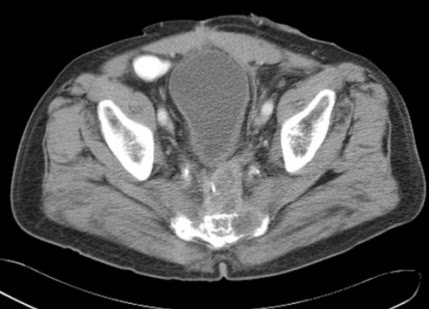

Fractura del sacro postraumática. Imagen axial TC revela una fractura que afecta los forámenes neurales en la mitad derecha del sacro.